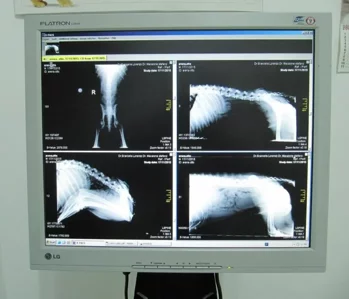

L’ambulatorio disponde di apparecchiature per radiologia digitale di alta qualità attraverso un sistema CR indiretto, senza utilizzo di pellicole deteriorabili nel tempo. Si evitano quindi prolungati tempi di esposizione dell’operatore e del paziente dovuti a ripetizioni frequenti causate da errori tecnici o di sviluppo.

In oltre ci occupiamo di radiologia preventiva per l’individuazione precoce di alcune delle malattie scheletriche ereditarie più comuni come la displasia dell’ anca e del gomito.